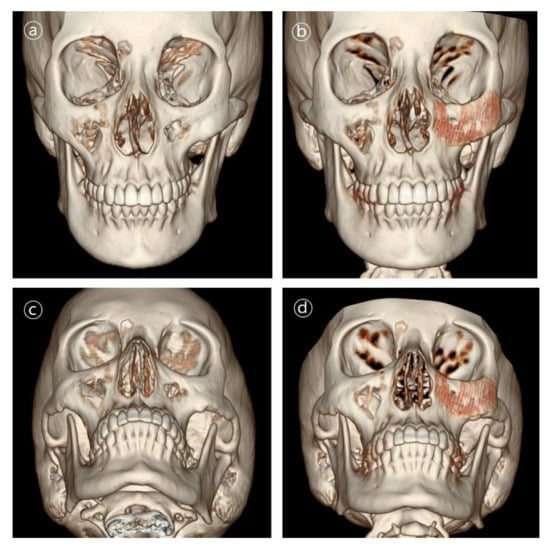

Figure 6. 3D CT images in patient #1. Contour and symmetry of left zygomatico-maxillary region was restored with de novo bone formation. (a,b) Pre- and postoperative 6-month frontal view CT images. (c,d) Pre- and postoperative 6-month basal view CT images.

Patient #1 was 21-year-old female who underwent delayed reconstruction 24 months after ablation of intraosseous hemangioma. The maxillary bone defect was exposed using the gingivobuccal and transconjunctival approaches. A 3D-printed PCL/β-TCP scaffold was fitted into the defect, and the patient required no further resection of the bony structures. The implant was fixed using a resorbable plate and screws made of HA-PLLA (hydroxyapatite/poly-l-lactide (Figure 5 and Figure 6).